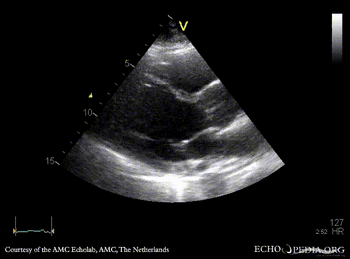

PLAX: no opening of aortic valve PLAX zoom